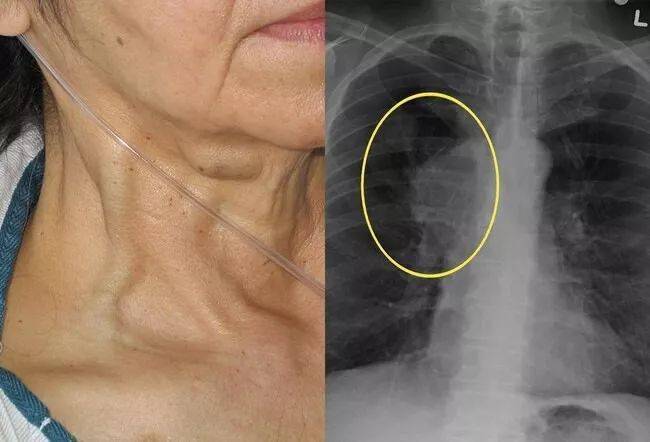

上腔静脉综合征可能会导致气道受压,喉头水肿,胸腔积液和脑水肿.